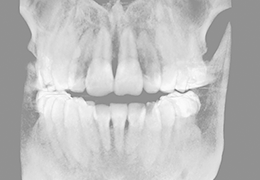

View X-Ray CT & MRI Scans Fast and Easily

Designed for surgeons, Pro Surgical 3D makes it easy to view patient scans quickly. Pro Surgical 3D facilitates the optimal 3D treatment and assessment workflows based on X-ray CT and MRI scans – and best of all, it’s FREE!

Designed mainly for CT and MR DICOM modalities.

Multi-planar slicing.